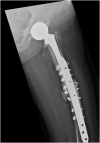

We report an 85-year-old patient with severe osteoporosis who had suffered from multiple episodes of periprosthetic fracture of the femur. Revision fixation with long-spanning cable plate for bisphosphonate-induced atypical periprosthetic femoral fracture was performed. Nonunion and implant failure occurred at 16 months requiring revision surgery using long-stem femoral prosthesis with cable-plate fixation. To further facilitate bone healing, allograft and bone morphogenetic protein (BMP) were added. Eventually bone union was achieved after one year.